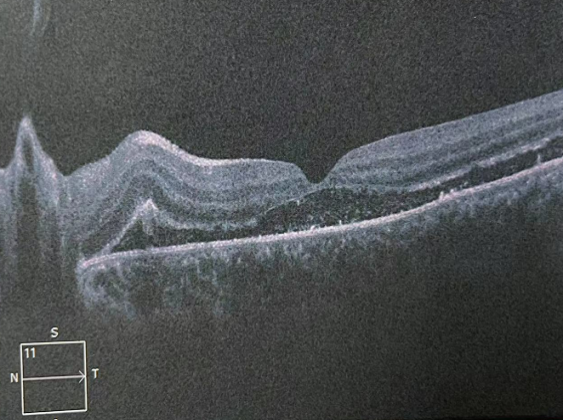

视网膜,这个名字听起来有些生僻,但它却是我们视觉系统的核心部件。就像一台精密的相机,眼睛捕捉光线,视网膜则负责将这些光线转换成图像,传递给大脑,让我们看到这个世界。视网膜是一层非常薄的膜,但它还可以分为十层结构。其中,靠内侧的九层合起来,叫做神经上皮层,最外面一层叫色素上皮层。我们所说的视网膜脱离,并非是整个视网膜掉下来,而是视网膜内九层与外一层分离了。如果视网膜出现问题,就好比相机的底片受损,图像就会变得模糊不清,甚至完全消失。

高度近视患者的眼轴比普通眼睛长,眼球比正常人大。随着眼轴拉长,球壁会变薄,周围血管变细,血供差。周围的视网膜组织会出现变性区域和小孔,临床上称为视网膜裂孔。一旦出现裂孔,玻璃体会沿裂孔渗漏到视网膜下,顶起视网膜,使视网膜色素上皮层与神经上皮层分离,出现视网膜脱离,患者出现明显的视野缺损、视力下降等。

已经发生视网膜脱离的患者需要手术治疗。手术可以根据视网膜裂孔的位置、数目,大小,视网膜脱离的范围,时间,视网膜周围有无牵拉及玻璃体液化的程度分为内路和外路手术。内路手术主要是玻璃体切割术联合视网膜复位手术及激光光凝术,是从眼球内进行手术。外路手术主要是巩膜外压术和巩膜环扎术,从巩膜外进行手术,不进入眼球内部。